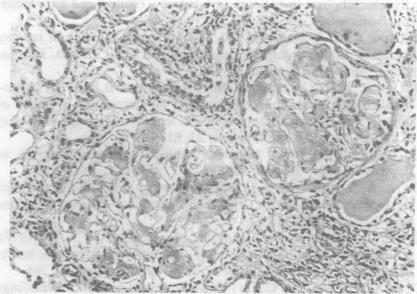

Sixty consecutive patients with leprosy were investigated for renal involvement. Clinically overt renal disease was present in 4 patients; 3 presented with a nephrotic state and one patient with progressive renal failure. Urinalysis showed daily protein loss ranging from 0.4 to 8.9 g in 8 patients and microscopic haematuria in 4 cases. Elevated levels of blood urea and creatinine were seen only in one patient with diffuse proliferative glomerulonephritis. Of the 36 patients in whom distal tubular functions were evaluated, concentration and/or acidification defects were detected in 9 patients (25%). Renal histology revealed no abnormality in any of these patients. Serum C3 levels were decreased in 5 patients with lepromatous leprosy and 3 patients with borderline leprosy. Histological evidence of renal involvement was detected in 9 patients (15%). Amyloid deposits were seen in 3 (5%) patients of whom 2 had lepromatous leprosy and one had tuberculoid leprosy with chronic trophic ulcers. Mesangial proliferative lesions were seen in 5 (8.3%) and diffuse proliferative lesions (with crescents in more than 70% of glomeruli) in one patient. All of them had lepromatous leprosy. Three of the 5 patients with mesangial proliferative glomerulonephritis had erythema nodosum leprosum at the time of biopsy. Immunofluorescence studies revealed granular deposits of IgA, IgM and C3 in one patient with mesangial proliferation and IgA/IgM with or without C3 in 3 more patients in whom renal histology was normal. Glomerulonephritis associated with leprosy appears to be immune mediated but confirmation requires identification of lepra antigen in the glomerular immune complex deposits.

对60例连续性麻风患者进行了肾脏受累情况调查。4例患者存在临床明显的肾脏疾病;3例表现为肾病状态,1例表现为进行性肾衰竭。尿液分析显示,8例患者每日蛋白质丢失量为0.4至8.9克,4例出现镜下血尿。仅1例弥漫性增殖性肾小球肾炎患者出现血尿素和肌酐水平升高。在评估了远端肾小管功能的36例患者中,9例(25%)检测到浓缩和/或酸化缺陷。这些患者的肾脏组织学检查均未发现异常。5例瘤型麻风患者和3例界线类麻风患者的血清C3水平降低。9例(15%)患者检测到肾脏受累的组织学证据。3例(5%)患者可见淀粉样沉积物,其中2例为瘤型麻风,1例为结核样麻风伴慢性营养性溃疡。5例(8.3%)可见系膜增殖性病变,1例可见弥漫性增殖性病变(超过70%的肾小球有新月体形成),所有患者均为瘤型麻风。5例系膜增殖性肾小球肾炎患者中有3例在活检时出现结节性红斑。免疫荧光研究显示,1例系膜增殖患者的肾小球中有IgA、IgM和C3的颗粒状沉积物,另外3例肾脏组织学正常的患者中有IgA/IgM伴或不伴C3。麻风相关的肾小球肾炎似乎是免疫介导的,但需要在肾小球免疫复合物沉积物中鉴定麻风抗原才能确诊。